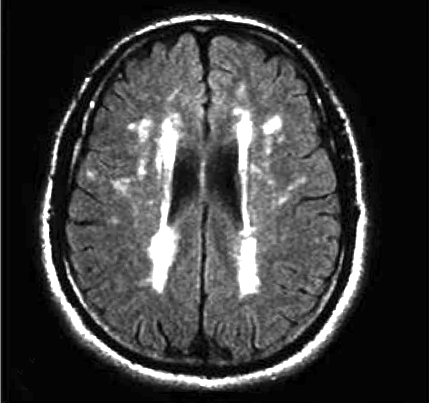

脑白质疏松症(Leukoaraiosis,LA)是在1987年加拿大神经学家Hachinski提出,leukoaraiosis这一名词由希腊文“leuko”(意为“白色”)和“araiosis”(意为“稀疏”)组成。脑白质疏松症是多种不同病因引起的一组以脑室周围及半卵圆中心区脑白质的弥漫性斑点状或斑片状双侧对称性缺血改变为主的临床综合征,这些改变在CT上为低密度,在MRI图像上为高信号的区域。

脑白质疏松症的发展有一定的模式,初期我们可以观察到脑室周围病变朝侧脑室边缘发展(如下图1),当问题加重时则呈现图2。